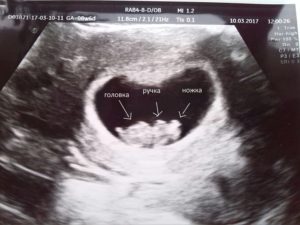

Заметив у себя симптомы, характерные для замершей беременности, обратитесь к гинекологу. Вас направят на УЗИ.

Может ли УЗИ ошибиться при диагностике замершей беременности? Да, может, если его делают на 5 неделе развития плода. В таком случае сердцебиение может ещё не определяться и в норме, тогда врач направит вас на повторное УЗИ через неделю. Рост плодного яйца и появление сердцебиения исключат замершую беременность.

- Последним этапом обследований станет УЗИ. С помощью ультразвукового обследования станет понятно, а бьется ли сердце у эмбриона или нет.

Вторым этапом диагностирования замершей беременности идет УЗИ матки и определение ХГЧ в крови.

В ранних сроках на УЗИ не определяется сердцебиение плода, размеры эмбриона не соответствуют норме или диагностируются анэмбриония (плодные оболочки имеются, а эмбриона нет).

- Ультразвуковое исследование – позволяет выявить наиболее достоверные признаки замершей беременности: отсутствие сердцебиения ребенка, анэмбриония;